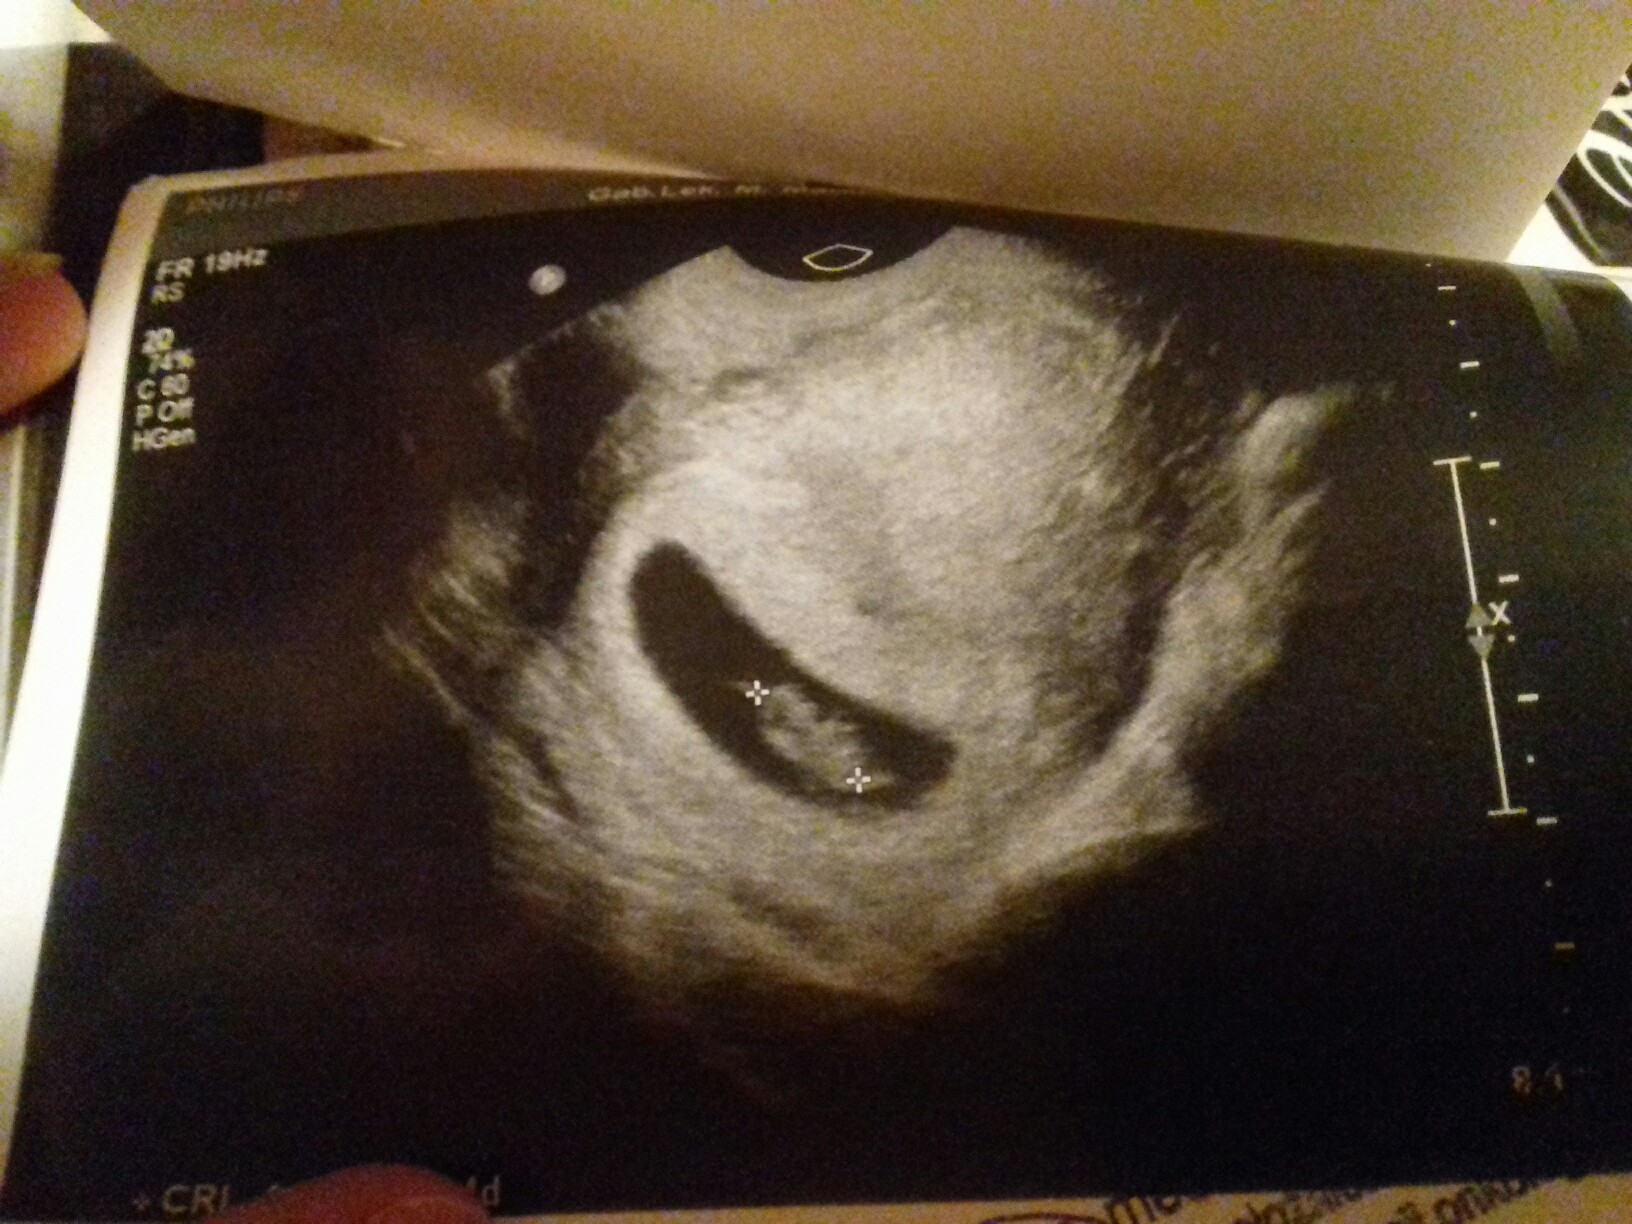

27.06.17 Anastazja [*]

Z miłości Nam dana - nigdy niezapomniana <3

. Nasza cudowna fasoleczka [emoji173]